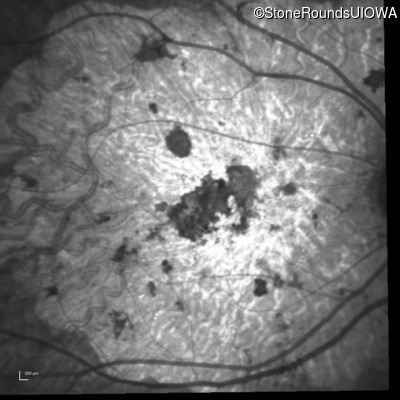

Infrared Fundus Photograph - Left - 20/300 sc

Exemplar